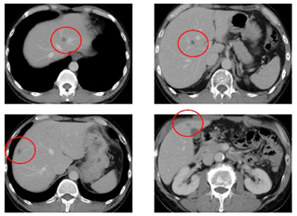

治療開始から19週(6コース)経過後CT所見で原発巣は縮小継続しているが 多発肝転移が出現 |